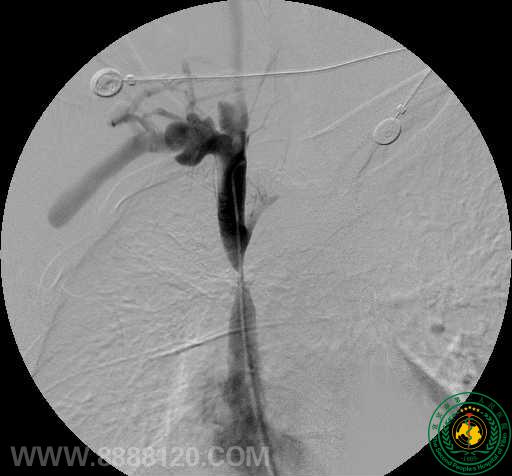

影像科介入组近日完成一例上腔静脉支架植入术

影像科介入组近日完成一例上腔静脉支架植入术3066